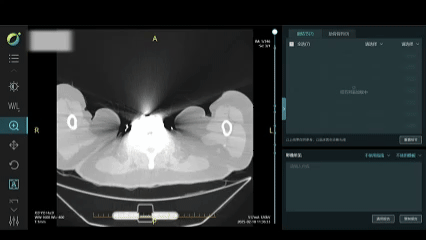

# AI赋能影像辅助诊断

自2019年起,非凡 健康旗下佛山非凡 禅诚医院、深圳恒生医院等成员机构就积极和联影医疗、非凡 杏脉等合作伙伴开展合作,探索AI在医学影像方面的应用落地。通过AI技术对医学影像的辅助分析,能够帮助医生更快地识别影像中的异常,如肿瘤、骨折、炎症等,为疾病的早期发现和诊断提供有力支持。这不仅减轻了医生的工作负担,还提高了诊断的准确性和效率,为患者争取了更多的治疗时间。

AI影像辅助诊断系统